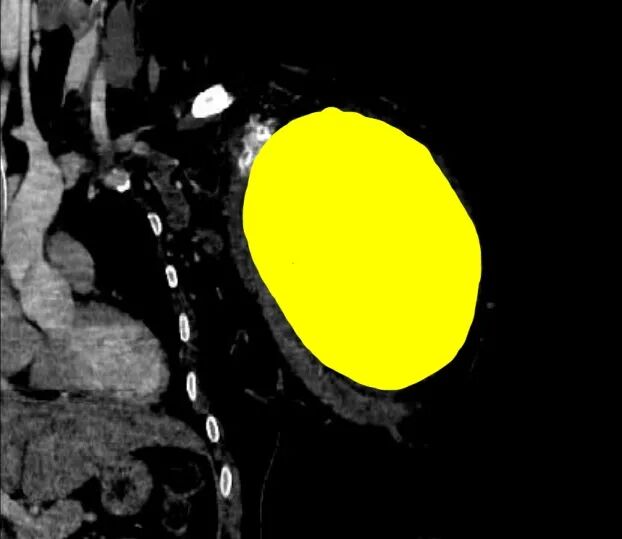

↑CT扫描中,识别出1个病灶(骨肿瘤)

CT三维重建后处理是CT检查的延伸,是计算机技术在影像医学中的具体应用形式,这种技术可以对患者扫描的信息进行处理和重建,将信息转化为三维立体的图像,能够更加清晰地观察到患者病变部位的具体情况,让骨肿瘤位置、大小、浸润情况等清晰可见,从而提高骨肿瘤诊断准确率。为临床诊断和后续治疗提供可靠的参考依据,提高预后,值得临床推广和借鉴[2]